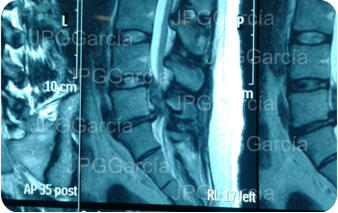

Hernia de disco lumbar extrusa L5 S1 (cortes

sagital y coronal en resonancia magnética)

Hernia de disco lumbar extrusa L5 S1 (cortes sagital y coronal en resonancia magnética)